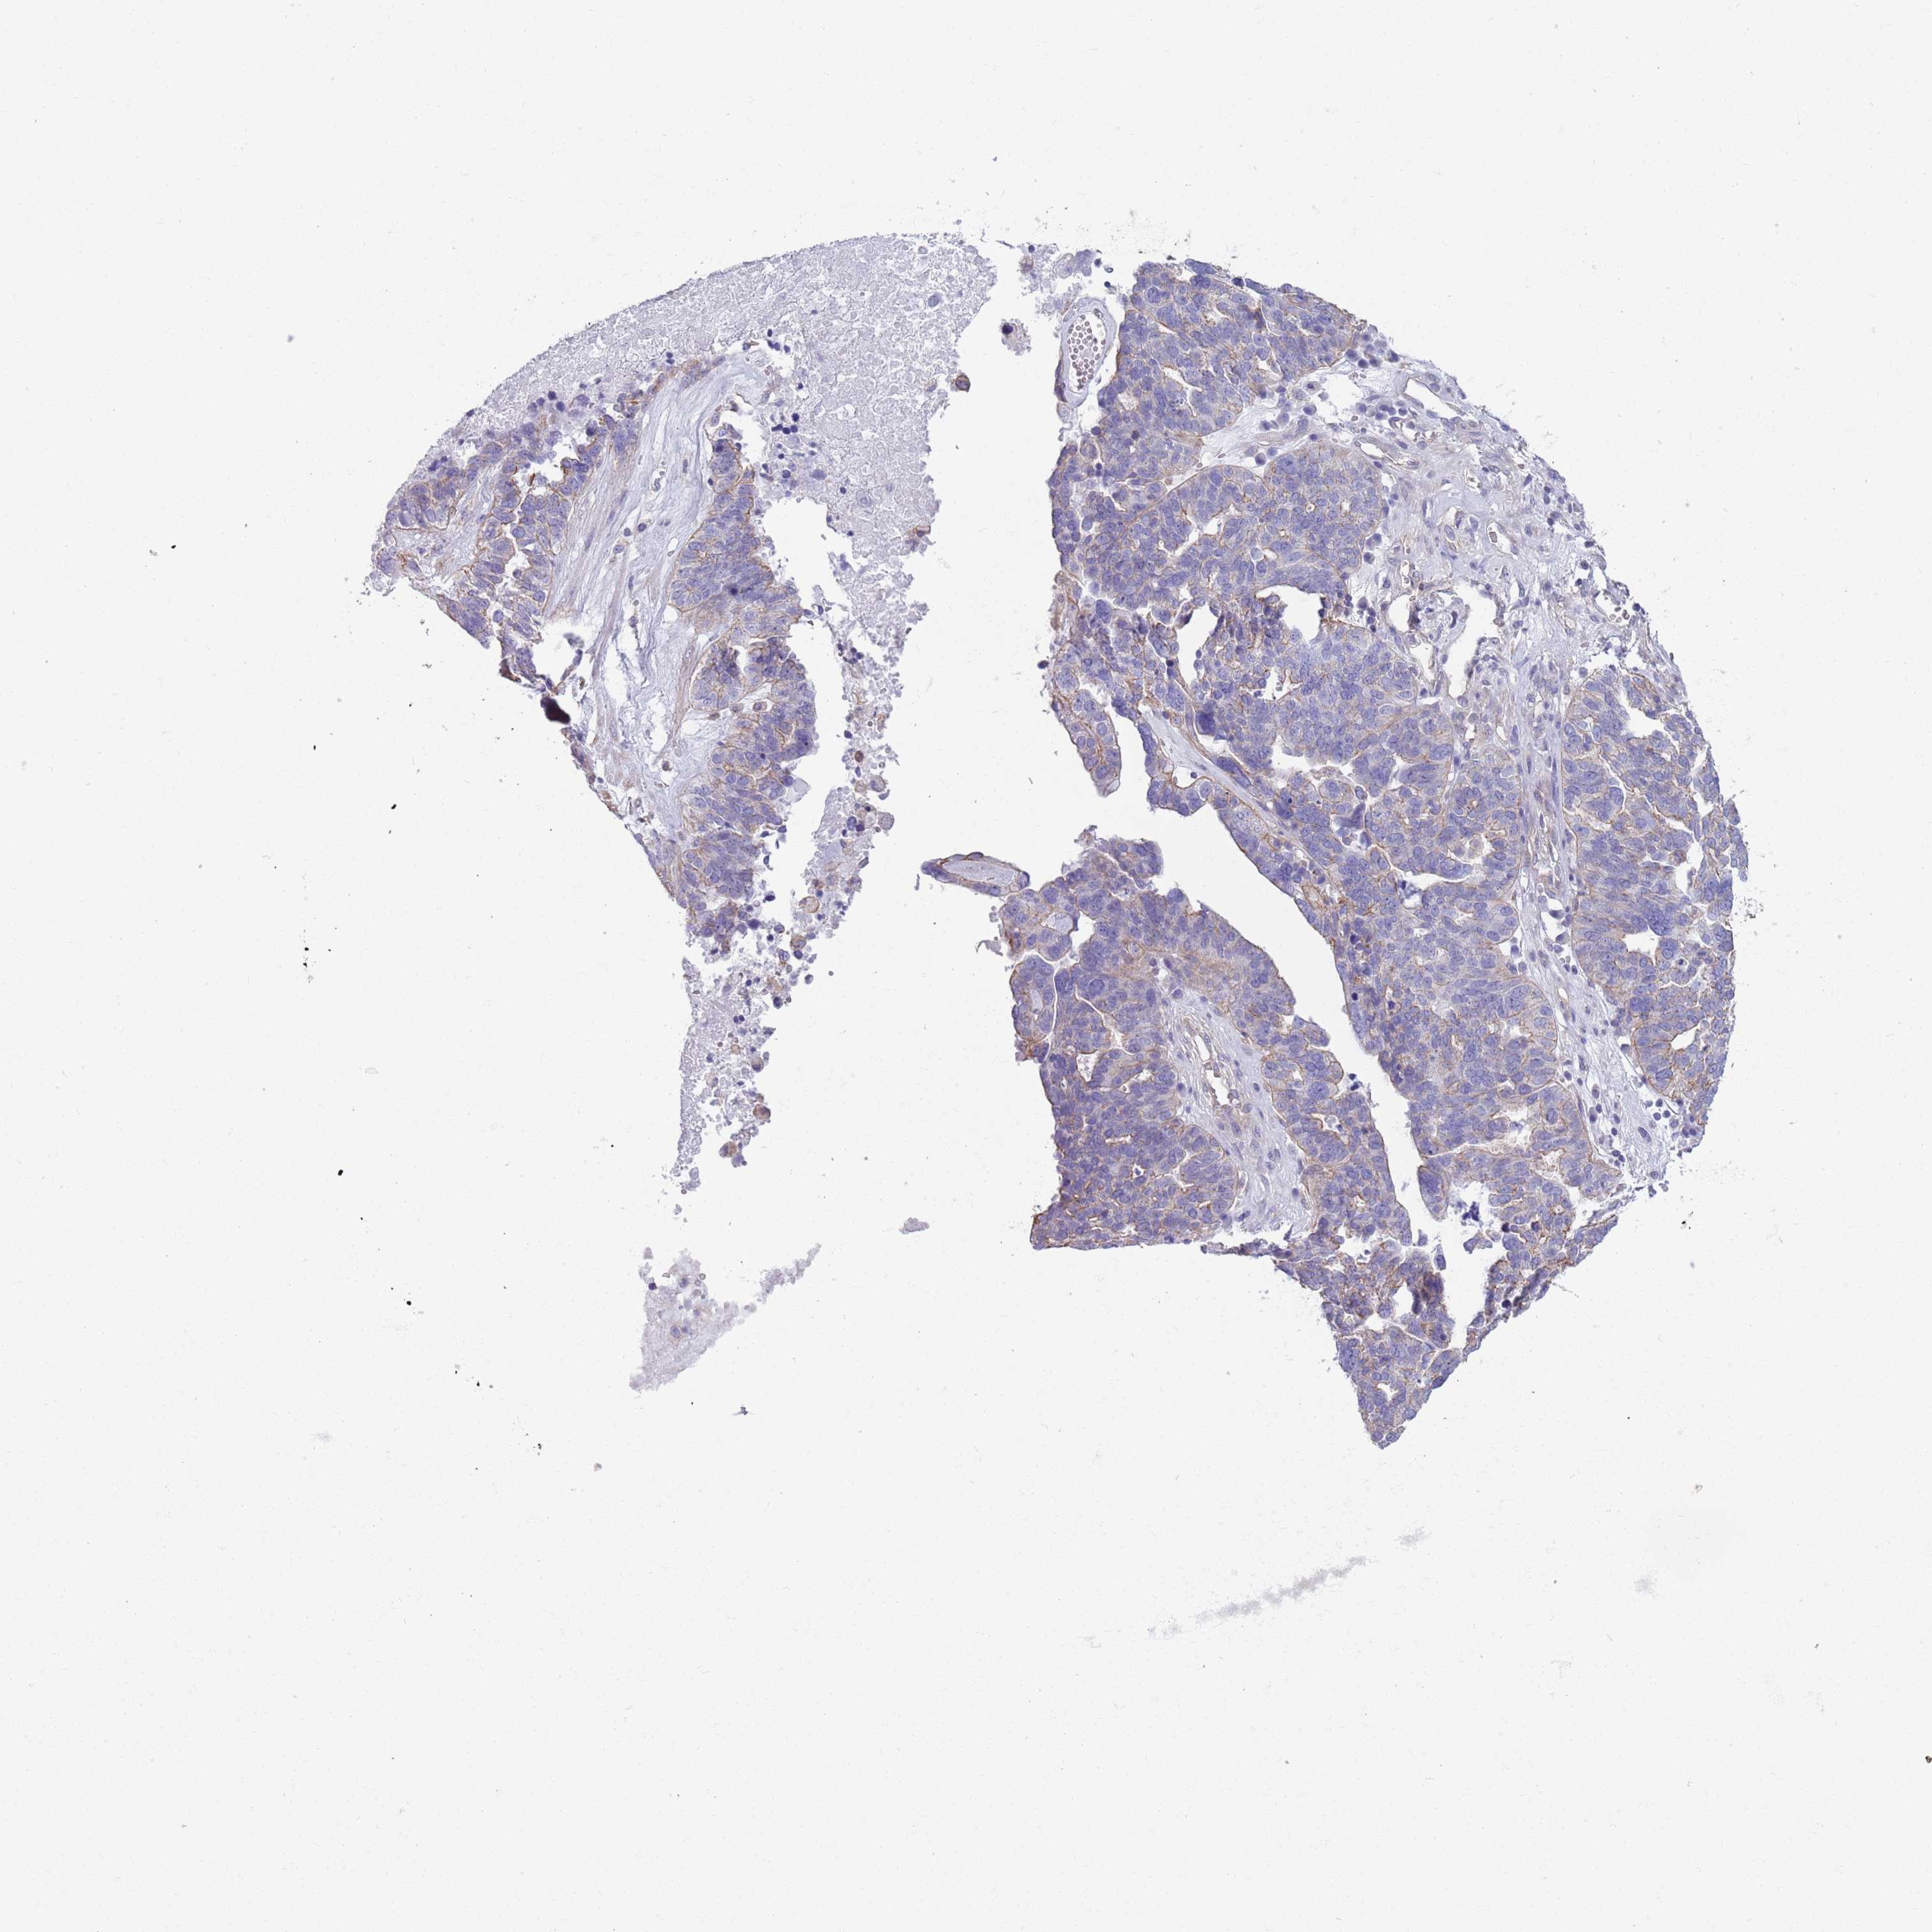

OVARIAN CANCER - Protein expressioni

A mouse-over function shows sample information and annotation data. Click on an image to view it in a full screen mode. Samples can be filtered based on level of antibody staining by selecting one or several of the following categories: high, medium, low and not detected. The assay and annotation is described here.

Note that samples used for immunohistochemistry by the Human Protein Atlas do not correspond to samples in the TCGA dataset.

Antibody stainingi

Antibody staining in the annotated cell types in the current human tissue is reported as not detected, low, medium, or high, based on conventional immunohistochemistry profiling in selected tissues. This score is based on the combination of the staining intensity and fraction of stained cells.

Each image is clickable and will lead to virtual microscopy that enables deeper exploration of all samples and also displays staining intensity scores, fraction scores and subcellular localization as well as patient and tissue information for each sample.

Antibody HPA041301

Antibody HPA044239